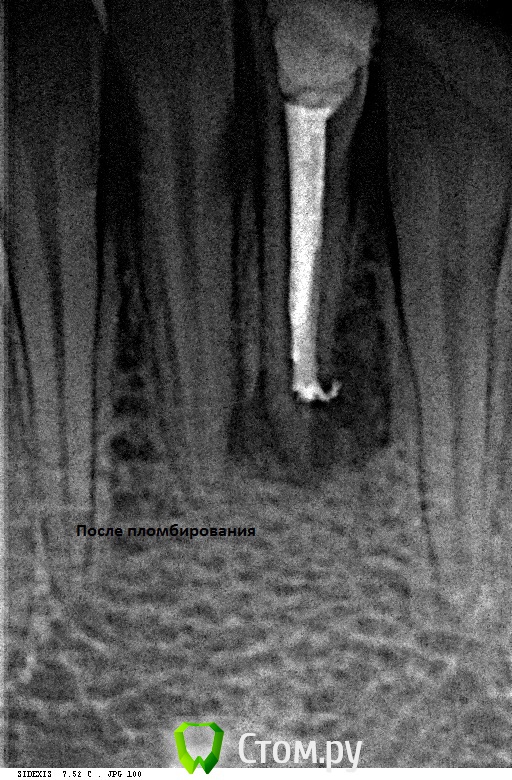

Alexandr Iv Опубликовано 29 июля, 2014 Поделиться Опубликовано 29 июля, 2014 Пациент Н. 14 лет.Диагноз: Хронический гранулирующий периодонтит зуба 3.1Зуб ранее дважды лечен эндодонтически. Корневой канал "обтурирован" проволокой. Был направлен на удаление. Хирург пригласил на консультацию. Решили "спасать". За час под микроскопом извлечена проволока (наверно, это проволока)) ) методом захвата в самодельный цилиндр (из носика для жидкотекучего) и заклиниваем проволоки в цилиндре с помощью 25 к-файла. Обработка и обтурация корневого канала. SoftCore + несколько дополнительных штифтов. Восстановление коронки зуба Filtek Ultimate. Каков на Ваш взгляд прогноз зуба и как Вы видите дальнейшее восстановление коронковой части? Ссылка на комментарий

Alexandr Iv Опубликовано 21 ноября, 2014 Автор Поделиться Опубликовано 21 ноября, 2014 Контрольный осмотр через 4 месяца.Жалоб нет. 2 Ссылка на комментарий